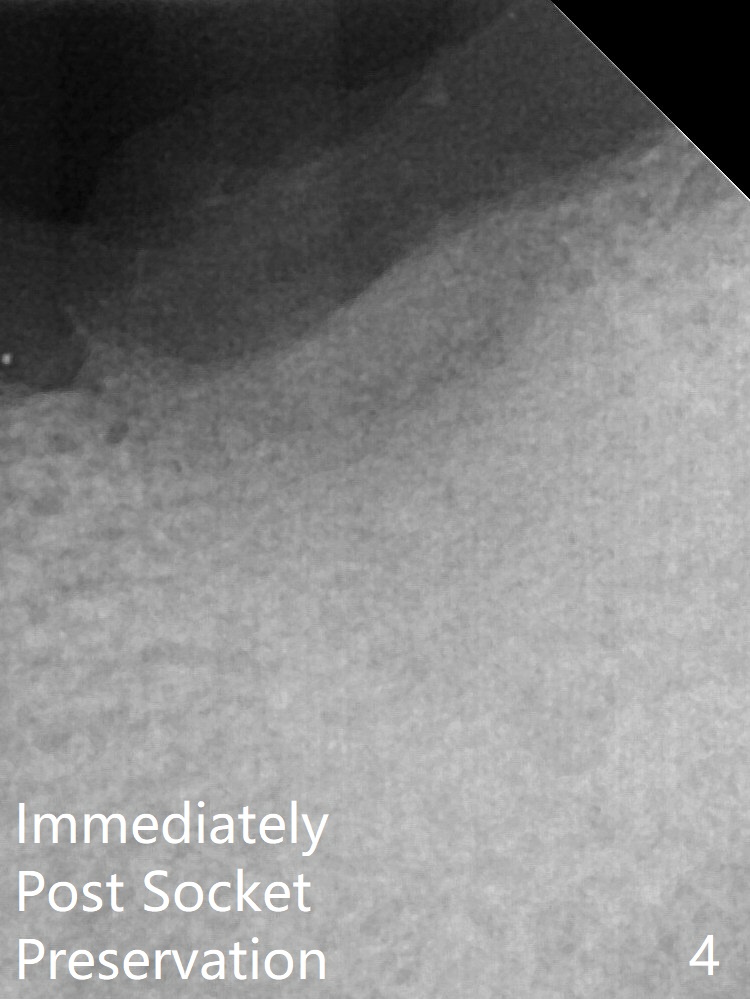

The upper portion of the socket has normal trabecular patterns 7 months post socket preservation (Fig.1, as compared to Fig.4 (immediately post socket preservation)).  The bone density of the upper portion of the previous socket increases 4.5 months post implant placement (Fig.2 *).